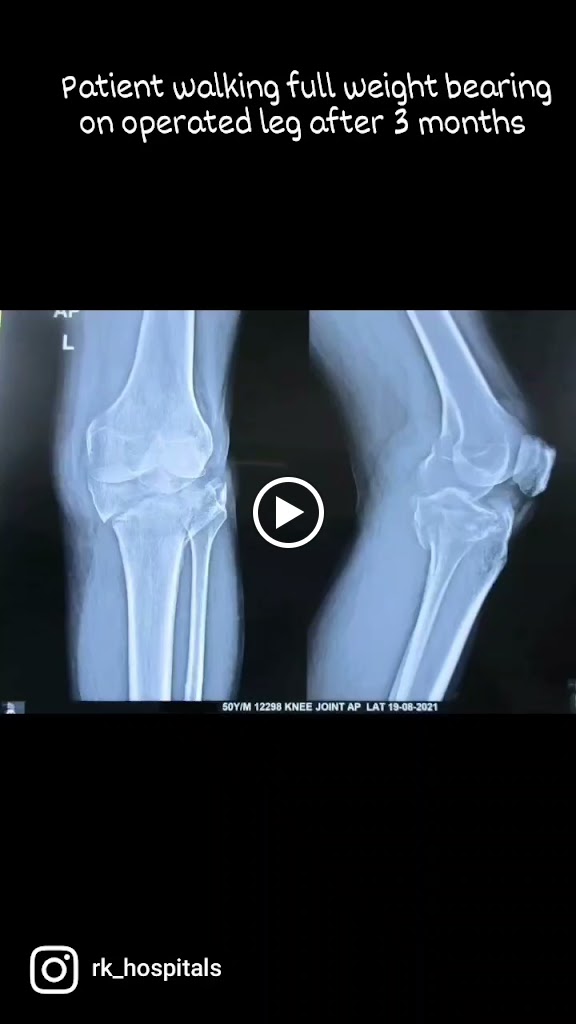

My mother had knee replacement surgery . She is fine now and her leg also good. Prashanth sir treatment is good. We felt good with his treatment and nicely he treated patients.